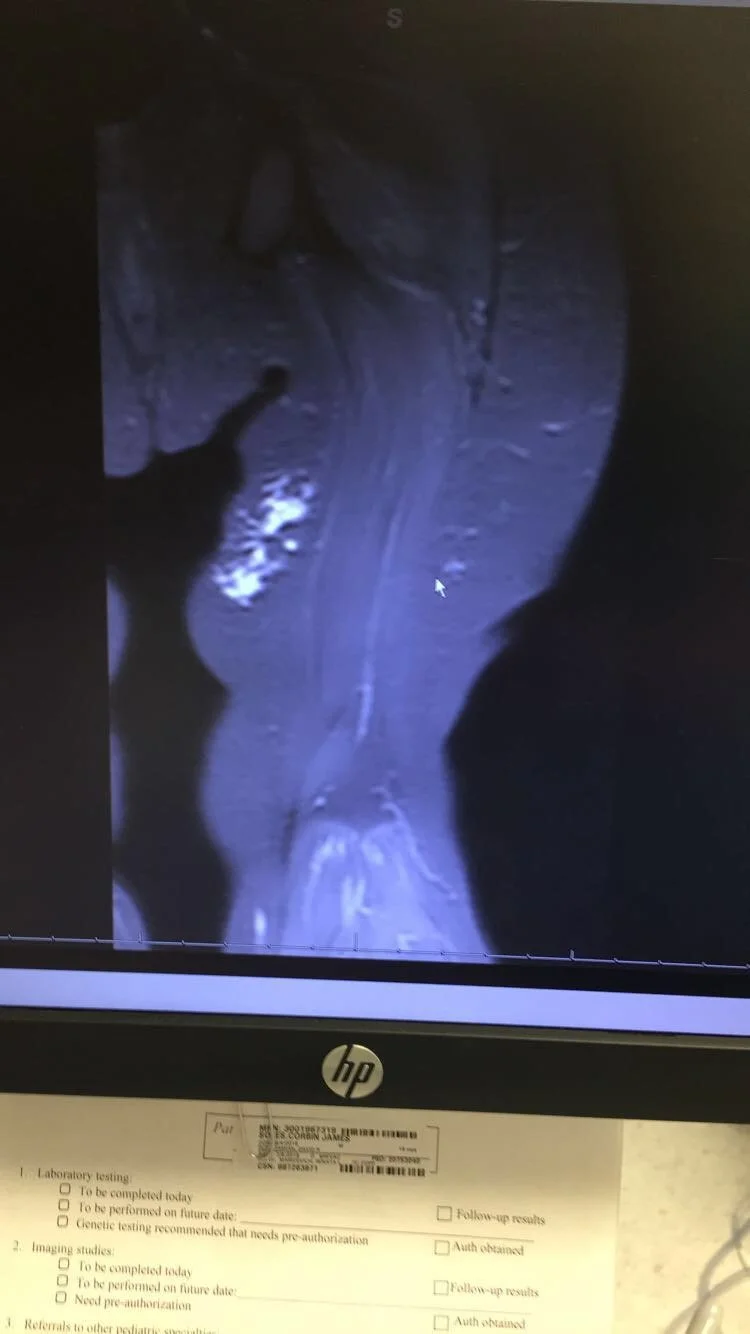

We went back for more tests. More ultrasounds. More MRIs. More waiting rooms. More unanswered prayers that turned into quiet tears.

That is when we finally got the diagnosis of lymphatic malformation.

In 2023, Corbin underwent sclerotherapy to try to shrink the cysts in his leg. They used bleomycin, a medication often used in cancer treatment. Sitting there knowing your child is receiving something that strong is terrifying, but you do it because you hope it will give them relief. It was about 60 percent successful. We celebrated that small victory even though we knew the fight was not over.